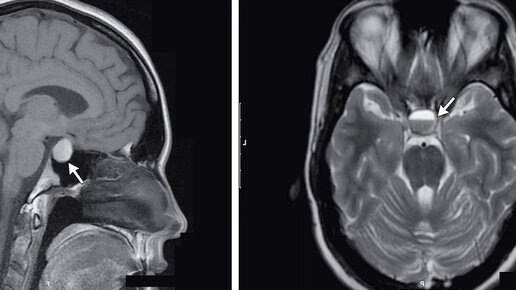

В диагностических центрах МРТ гипофиза используется: ЧТО ТАКОЕ МРТ ГИПОФИЗА МРТ гипофиза – это узконаправленный, прицельный метод диагностики гипофиза и тканей головного мозга, находящихся в зоне турецкого седла. Сложность обнаружения изменений в питуитарной железе способом объясняется его местом нахождения в основании головного мозга и маленькими размерами в диапазоне от 15 до 17 мм. Гипофиз играет важную роль в функционировании эндокринной системы человека. Орган отвечает за выработку гормонов, влияет на рост и обменные процессы в организме человека...

МРТ гипофиза – это наиболее информативный способ для выявления и оценки поражений питуитарной железы, а также окружающих ее тканей в зоне турецкого седла. Данное обследование не следует путать с МРТ головного мозга, где гипофиз тоже визуализируется, но менее четко и прицельно...